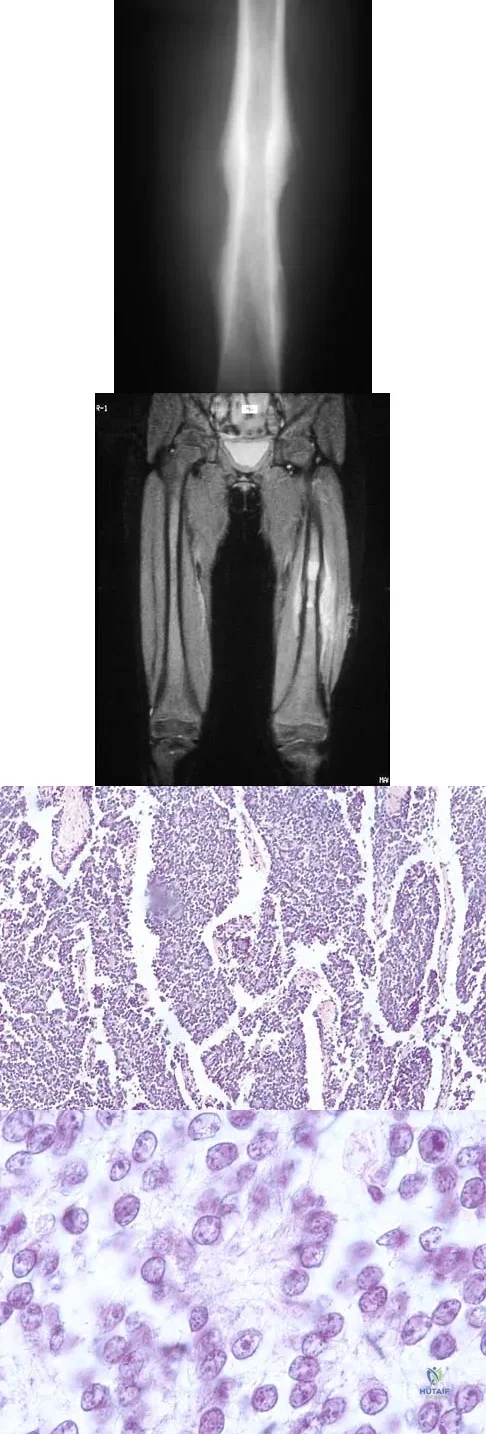

A 16-year-old girl injured her hip in a fall. Radiographs are shown in Figures 14a and 14b. She denies any history of pain prior to the fall and is currently asymptomatic. A bone scan, MRI scan, and biopsy specimens are shown in Figures 14c through 14f. What is the most likely diagnosis?

Although the classic radiographic appearance of fibrous dysplasia is one of a central metaphyseal lesion with ground glass matrix, it is not unusual to see either a more radiodense-appearing lesion or a more peripheral location. The histologic finding of spicules of woven bone without osteoblastic rimming in a bland fibrous background is diagnostic of fibrous dysplasia. The imaging studies could be consistent with low-grade osteosarcoma, osteoblastoma, or osteomyelitis, but all have a very different histologic picture. Observation is indicated in the absence of symptoms, impending fracture, or deformity. Fibrous dysplasia most commonly occurs in the proximal femur. Huvos AG: Bone Tumors: Diagnosis, Treatment, and Prognosis. Philadelphia, PA, WB Saunders, 1991, pp 30-43.